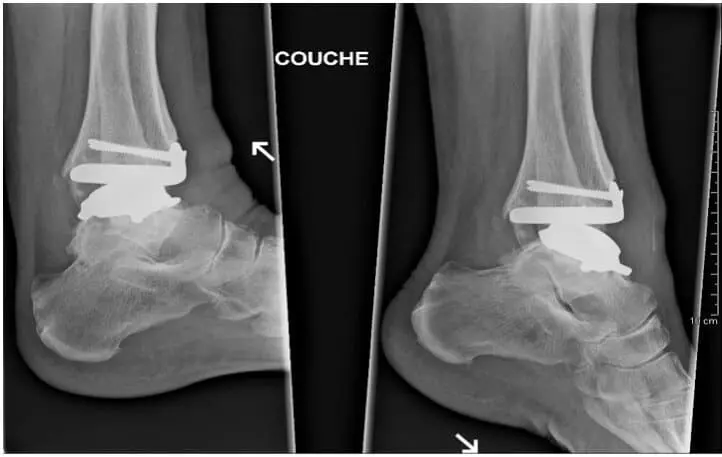

Prosthesis: With this, the diseased joint is replaced with an artificial joint. If adjacent joints, whether or not symptomatic, show signs of osteoarthritis, and in case you persist in maintaining the joint mobility, we can implant a prosthesis.

Recently, there is a reimbursement for the various components of the prosthesis, but only in certain cases. In addition, there has to be a correct follow-up in the years after the operation.The advantages are the preservation of motion, through which one protects the adjacent joints, and the fact that patients – if wearing a walker – are allowed to lean after 3 weeks already. However, the major disadvantage is that a prosthesis of the ankle has a shorter life span than at the knee or hip. Often, one has to perform a revision with prosthesis or arthrodesis after 10-15 years.